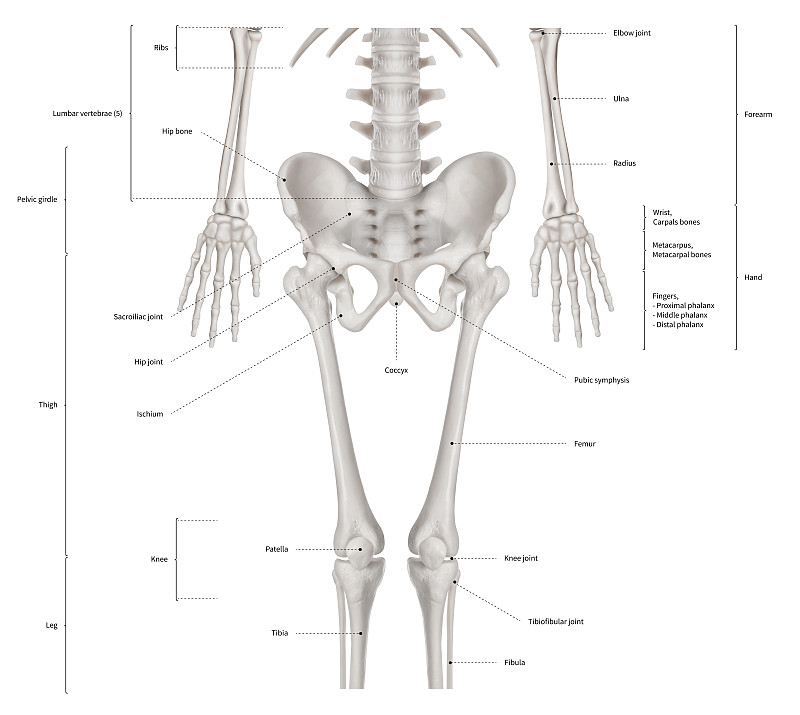

解剖。详情

EPS